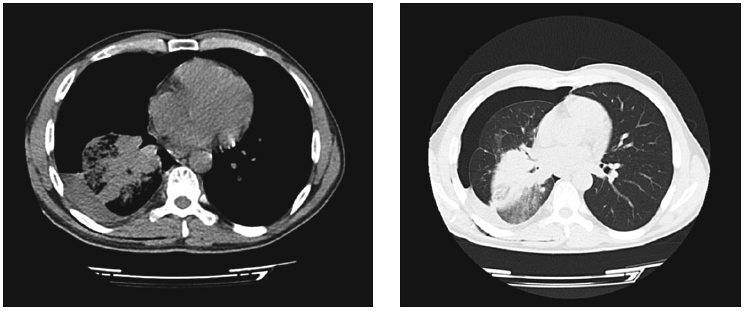

За время пребывания больного в КРО было выполнено исследование крови на Д-димер, уровень которого оказался в результате значительно превышающим норму и составил 3,2 нг/мл. Исследование крови на тропонин показало отрицательный результат. Кроме того, была выполнена ЭхоКГ, продемонстрировавшая значительную легочную гипертензию, гипертрофию левого и правого желудочков, а также снижение фракции выброса до 48 % (рис. 2).

Рис. 2. Эхокадиографическая картина пациента Г. при поступлении в КРО